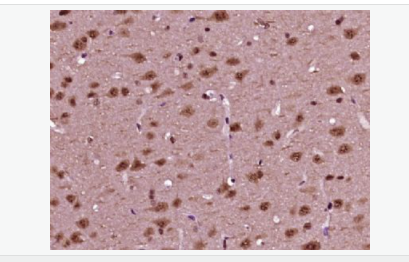

磷酸化神經細胞分化因子1抗體

Rabbit anti-phospho-NeuroD1 (Ser274) Polyclonal antibody

交叉反應:Human,Mouse,Rat(predicted:Pig,Cow,Sheep) 推薦應用:WB,IHC-P,IHC-F,ICC,IF,ELISA

中文名稱磷酸化神經細胞分化因子1抗體

別    名NeuroD1 (phospho S274); p-NeuroD1 (phospho S274); atonal; basic helix loop helix transcription factor; BETA 2; Beta cell E box transactivator 2; BETA2; BHF 1; BHF1; bHLHa3; class A basic helix loop helix protein 3; Class A basic helix-loop-helix protein 3; MODY 6; MODY6; NDF1_HUMAN; NEUROD; NeuroD1; Neurogenic differentiation 1; Neurogenic differentiation factor 1; neurogenic helix loop helix protein NEUROD; NIDDM.

產品應用WB=1:500-2000 ELISA=1:5000-10000 IHC-P=1:100-500 IHC-F=1:100-500 ICC=1:100-500 IF=1:100-500 (石蠟切片需做抗原修復)

細胞定位細胞核 細胞漿

免 疫 原KLH conjugated Synthesised acetylpeptide derived from human NeuroD1 around the acetylation site of Ser274:PL(p-S)PP

產品介紹This gene encodes a member of the NeuroD family of basic helix-loop-helix (bHLH) transcription factors. The protein forms heterodimers with other bHLH proteins and activates transcription of genes that contain a specific DNA sequence known as the E-box. It regulates expression of the insulin gene, and mutations in this gene result in type II diabetes mellitus. [provided by RefSeq, Jul 2008]

Differentiation factor required for dendrite morphogenesis and maintenance in the cerebellar cortex. Transcriptional activator. Binds to the insulin gene E-box.

Phosphorylated. In islet cells, phosphorylated on Ser-274 upon glucose stimulation; which may be required for nuclear localization. In activated neurons, phosphorylated on Ser-335; which promotes dendritic growth.

Defects in NEUROD1 are the cause of maturity-onset diabetes of the young type 6 (MODY6) [MIM:606394]. MODY is a form of diabetes that is characterized by an autosomal dominant mode of inheritance, onset in childhood or early adulthood (usually before 25 years of age), a primary defect in insulin secretion and frequent insulin-independence at the beginning of the disease.